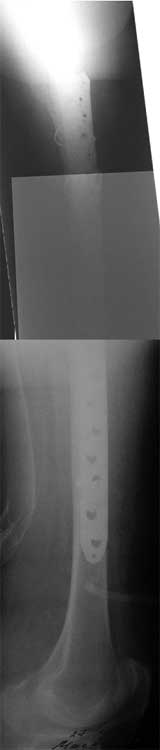

Re: Перелом бедра, через неделю после эндопротезир

на прошлой неделе прооперировали эту пациентку, рана заживает спокойно, начала ходить с костылями без опоры на поврежденную конечность.